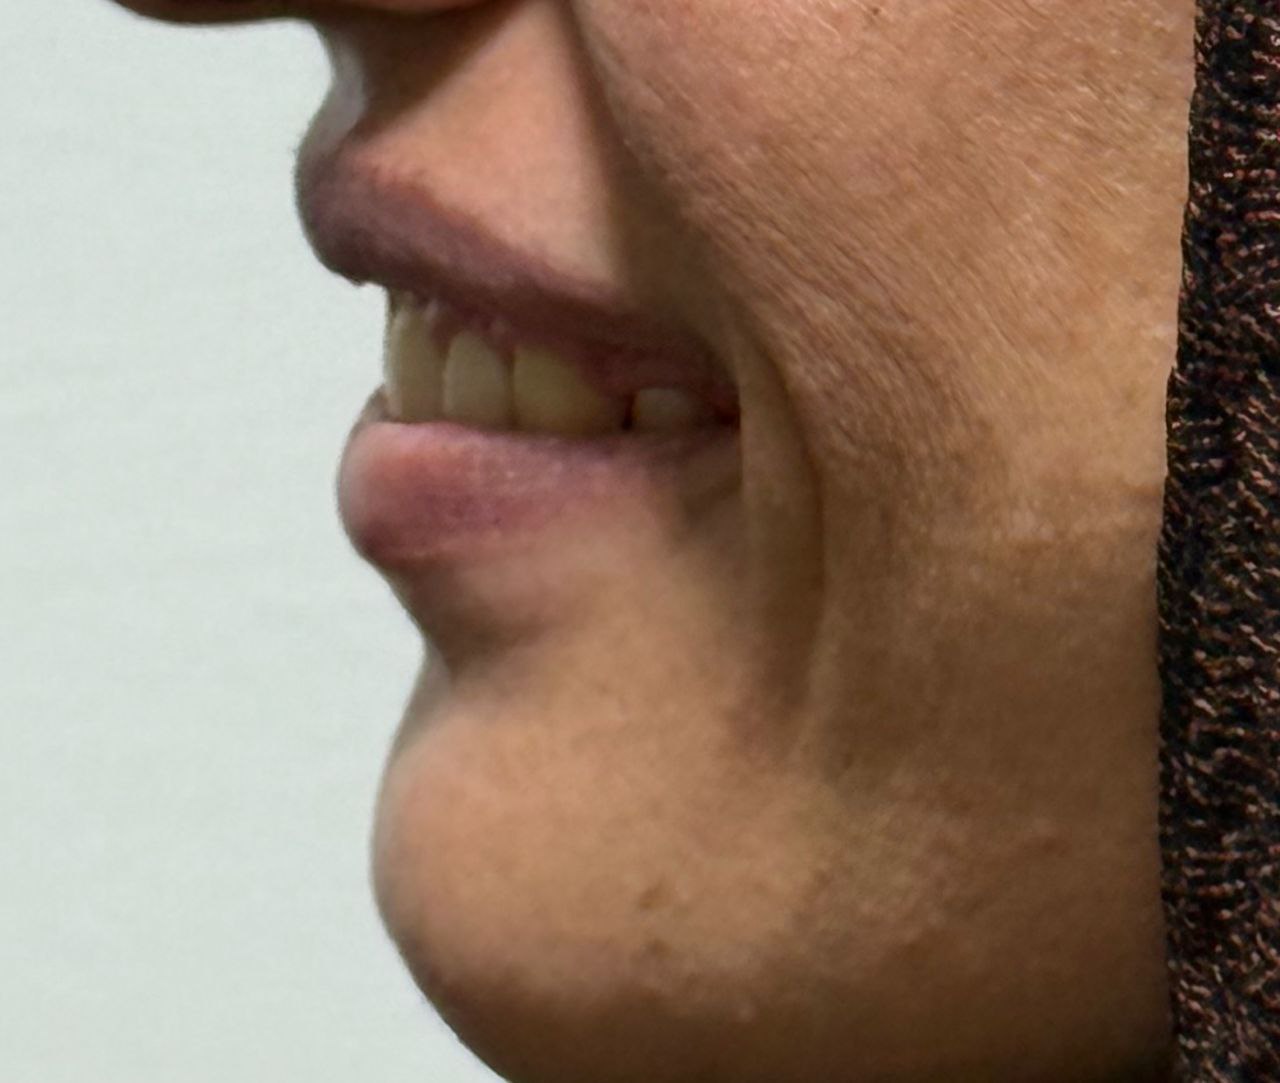

برخی از لبخند هایی که ساخته ایم

قبل و بعد جراحی فک